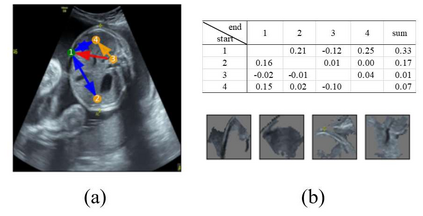

Although deep neural networks (DNN) have achieved state-of-the-art performance in various fields, some unexpected errors are often found in the neural network, which is very dangerous for some tasks requiring high reliability and high security. The non-transparency and unexplainably of Convolutional Neural Networks (CNN) still limit its application in many fields, such as medical care and finance. Despite current studies that have been committed to visualizing the decision process of DNN, most of these methods focus on the low level and do not take into account the prior knowledge of medicine. In this work, we propose an interpretable framework based on key medical concepts, enabling CNN to explain from the perspective of doctors' cognition. We propose an interpretable automatic recognition framework for the ultrasonic standard plane, which uses a concept-based graph convolutional neural network to construct the relationships between key medical concepts, to obtain an interpretation consistent with a doctor's cognition. Extensive experiments have empirically shown that our model can meaningfully explain the decision of the classifier and provide quantitative support.